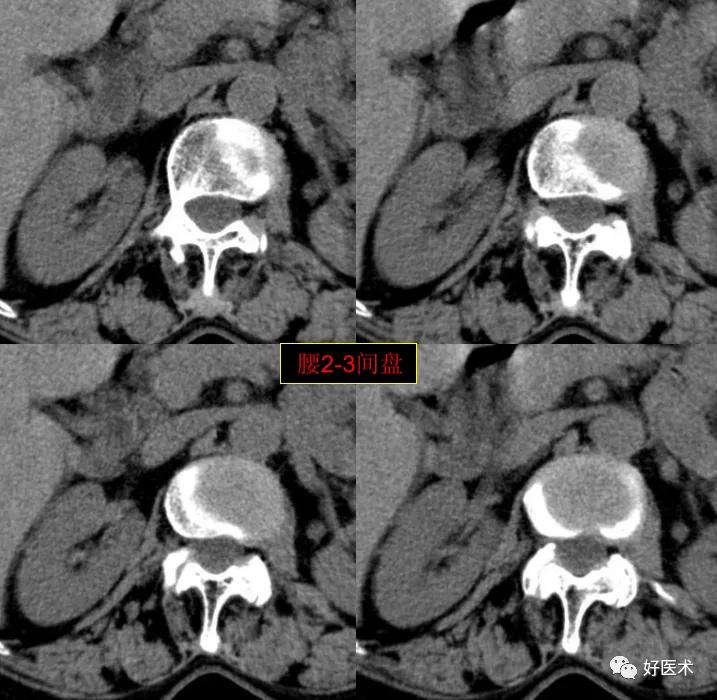

腰2-3间盘未见著变。

发现了什么?左侧竖脊肌较右侧明显肿胀饱满, 肌间脂肪间隙消失!!

终于知道了是什么鬼在作乱, 找到了左侧竖脊肌肿胀的元凶:肺癌转移。